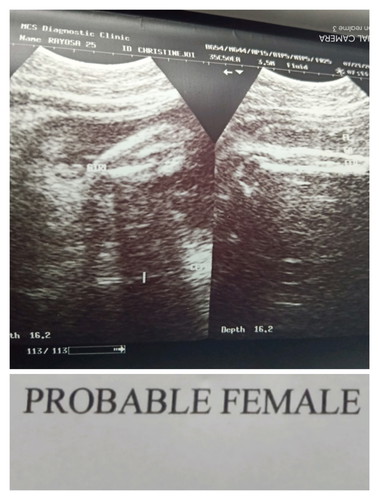

Finally π Girl talaga sya . nag alinlangan kasi ako nung unang ultrasound ko kasi Breech position tapos nakataob si baby pero sabe parang Girl So naiisip ko naman nun baka mamaya sabe Girl tapos pag nanganak e Boy π Pero eto Girl talaga sya. Team Septemberπ